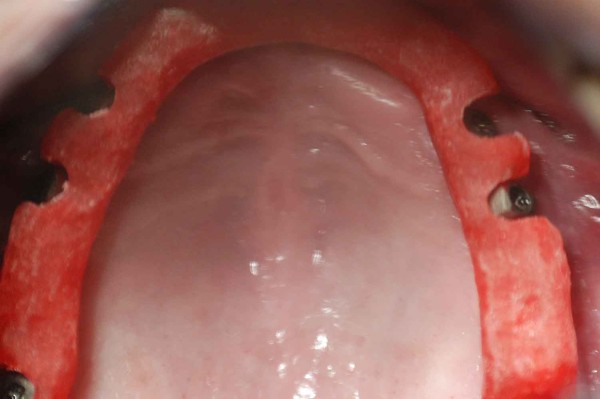

ABSTRACT La literatura oclusal se ha encargado de describir distintas funciones de la misma a través de los tiempos. El presente caso se realiza en forma de sobredentadura (over denture) debido a que la carencia de reborde óseo en el sector anterior verificado tanto clínicamente como mediante telerradiografía , impedía llevar a cabo una prótesis fija , por lo que se optó por un sistema de pilares ceramizados y paralelizados mediante el sistema SIRIUS, sobre seis implantes, y la conexión a una estructura de metal cerámica FIJA AMOVIBLE, mediante coronas telescópicas galvanizadas, otorgando al sistema la rehabilitación mediante una PIA(Prótesis Implanto Asistida con reposición ósea y gingival mediante porcelana rosa.) MATERIAL Y MÉTODOS: IMPLANTES:KLOCKNER SK-T.T.S. MONTAJE Y REGISTROS: ARCO FACIAL ESTÁTICO Y ARTICULADOR PRIMARIA: Abuttmets Ceramizados (I.P.S. D.SIGN IVOCLAR) SECUNDARIA: Cofias Galvanoformadas (AURO GALVAN CROWN WIELAND) TERCIARIA: Férula de Porcelana sobre Metal (I.P.S. D. SIGN IVOCLAR) CEMENTADO INTERFASE: NIMETIC CEM-ESPE DESARROLLO Se presenta el paciente a la consulta requiriendo la resolución de su maxilar inferior, el que se restaura mediante una férula de metal porcelana , en la que se preparan los lineamientos oclusales ideales (Spee-Wilson-Cuatro Niveles-etc) a fin de tener un sustrato de trabajo correcto, para la confección del maxilar superior, que porta una Prótesis Total convencional. Se estudia mediante Panorámica, Dentascan y Montaje en articulador semi ajustable. Se instalan seis implantes Klockner con Técnica Semisumergida pensados para una Carga diferida a tres meses después de la implantación Se realiza el arrastre de los Transfer mediante cubeta individualizada y fenestrada. Se confeccionan los abuttmentes correspondientes y se llevan a boca mediante una férula de posicionamiento realizada en Acrílico Duralay, el que por sus condiciones de carencia de cambios volumétricos verifican el correcto ajuste de los mismos Se ceramizan los abuttments y se paralelizan mediante el sistema SIRIUS, llevándolos a boca y chequeando su instalación Se confecciona una Prótesis Total Provisional que llevará el paciente durante el período de Osteointegración Se procede a la confección en laboratorio de las cofias galvánicas Sobre un nuevo modelo mayor se confecciona la férula de metal que uniremos en boca a las cofias galvanizadas mediante un cemento especial, una vez confeccionada la porcelana. Se prueba en boca la férula metálica, verificando su holgura que será ocupada por el cemento antedicho, y se comienza con el montaje de la cerámica y la verificación de los patrones oclusales de la misma. Se instala el todo haciendo morder al paciente con el medio cementante instalado. FIGURA 40 FIGURA 41 FIGURA 42 CONCLUSIONES La función de «GUIA CANINA», como esquema mas propicio para cumplir con los deseos de «autoprotección » de un SEG, rehabilitado o no, no se cumple al 100 % en casos como el presentado. La razones por las cuales el uso de la misma en lo que se da en denominar OCLUSIÓN MUTUAMENTE PROTEGIDA consiste en tres factores que detallo a continuación: A. En una función desoclusiva realizada por las piezas anteriores, como por ejemplo el canino, el BRAZO DE RESISTENCIA generado en la palanca desoclusiva, es por lo menos igual al brazo de potencia desarrollado, argumento de gran peso para hablar de la Desoclusión Canina como esquema de elección- B. La inclinación de los rebordes marginales del canino superior, esta dentro de los 70º, a diferencia de la tabla oclusal posterior que puede variar entre los 20 y 40 º. C. El estimulo que generan los dientes anteriores se dirige por via aferente al SNC, exitando por vía eferente, fundamentalmente al músculo temporal en sus fibras anteriores o VERTICALES…fibras de mucha menos capacidad de fuerza, que si la acción la ejercieran las fibras de la cincha PTERIGO MASETERINA, que serían exitadas en el caso de una Función de Grupo. EN EL CASO PRESENTADO LAS DOS PRIMERAS RAZONES TIENEN VIGENCIA. Sin embargo la última de ellas , al no tener los Implantes terminaciones nerviosas como las que posee el periodonto , los estímulos que llegan al SNC no se cumplen, y por lo tanto no existe la respuesta que por conducción eferente estimularía al músculo temporal a su acción. De la misma manera, el hecho que estos Implantes estén ferulizados , trasmite fuerzas laterales también a los posteriores, y no solo a los que actúan como caninos. El beneficio de las dos primeras razones de uso de una Función Canina en un caso como este, obedece a que de por si las mismas minimizan la acción direccional de las fuerzas, las que sin embargo son compartidas por las piezas posteriores tanto del LT como del LnT. En este compartir de la función, me resulta conveniente denominar a este esquema: FUNCIÓN DE GRUPO POSTERIOR DE ACCIÓN CANINA. ———————————————————————————————————- PIE DE FOTOS: 37: CASO TERMINADO